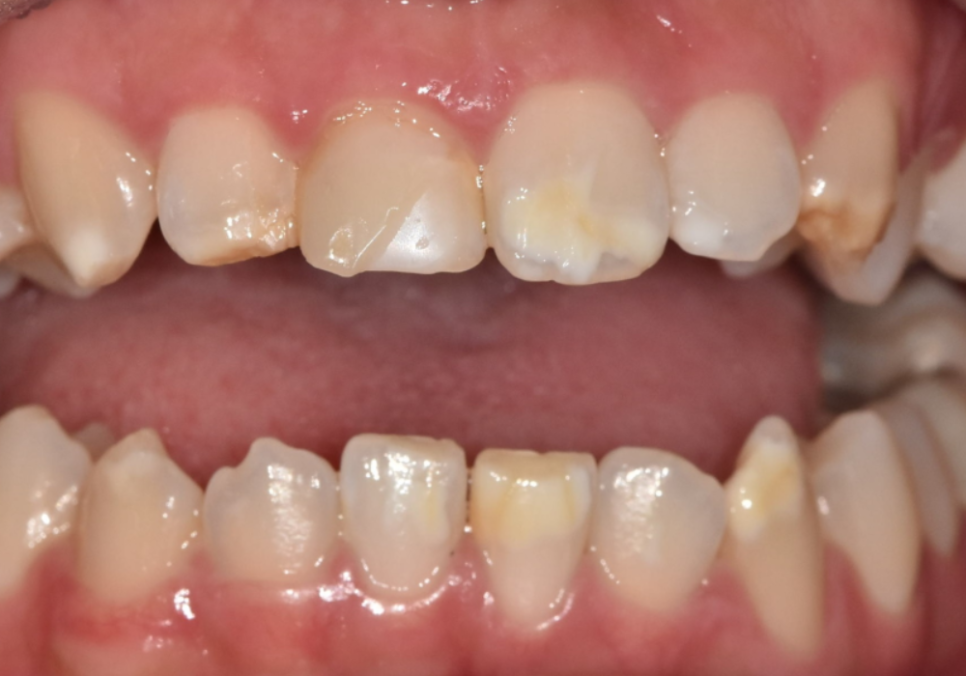

이번 환자분은 10대였고,

위 앞니 전반에 하얀 반점이

비교적 넓게 퍼져 있었습니다.

일부 치아는 반점이

치아 면적의 절반 이상을 차지해

앞니 톤이 균일하지 않은 상태였습니다.